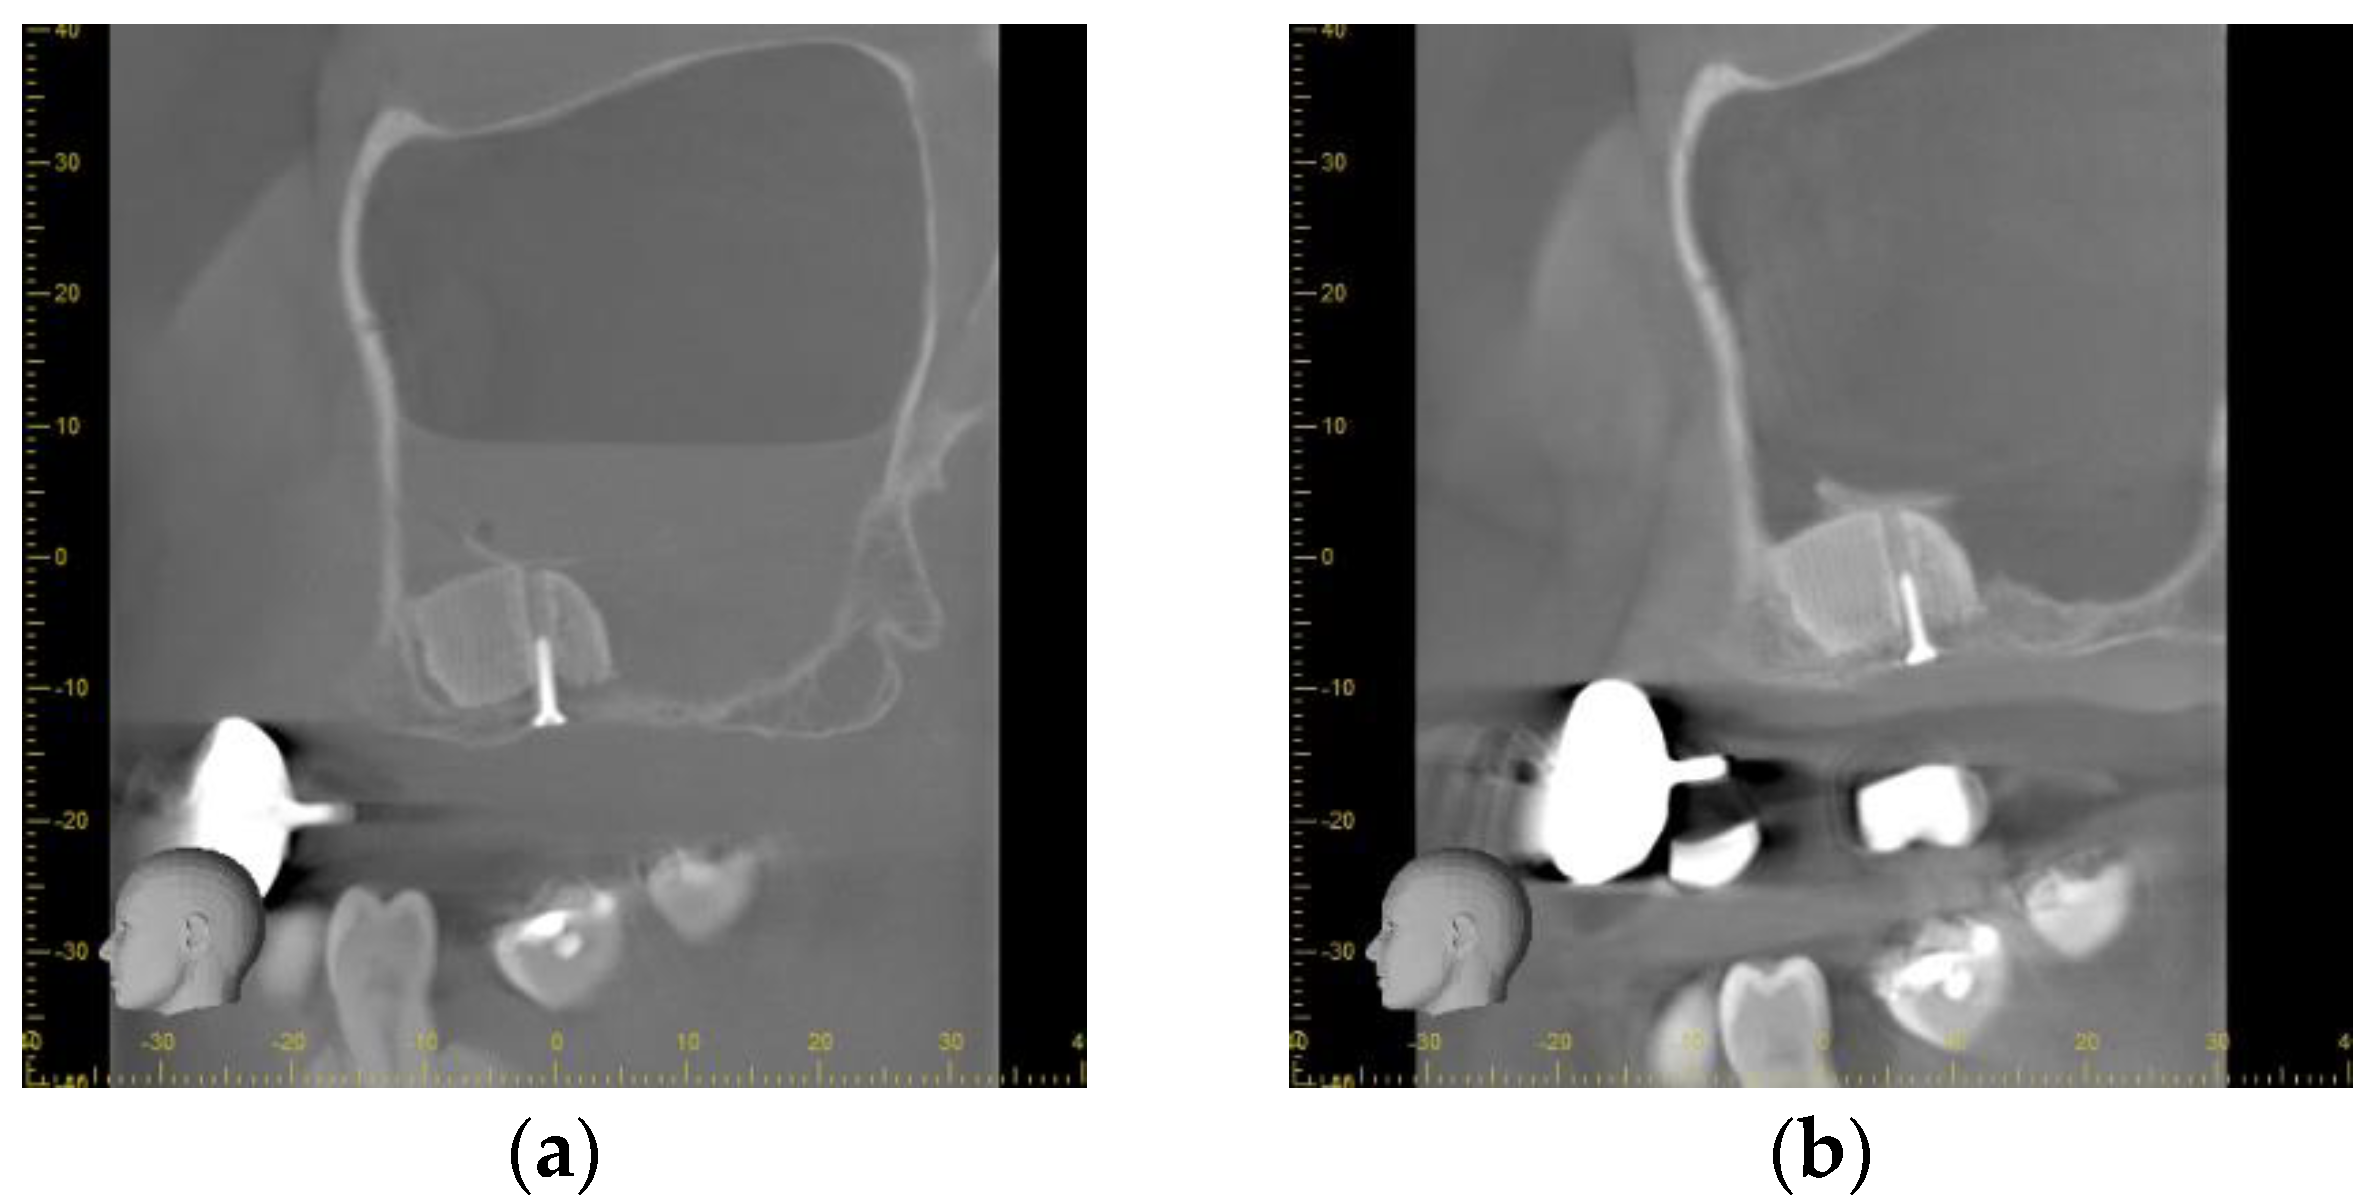

Directly after the insertion of the bone substitute, the cone beam computed tomography confirmed the correct position of the scaffolds according to the planned position. On the left side, a slight gap between the palatal bone wall and the scaffold was observed. The bone lids used to access the sinuses were located on the cranial site of the scaffolds. As a consequence of the small perforation of the Schneiderian membrane, a level of liquid was obvious in the left maxillary sinus whereas on the right side a slight swelling was observed (Figure 5a).

Figure 5.

Radiographical outcome (a) Sagittal plane of the left maxillary sinus directly after augmentation. An air-fluid-level of blood is visible after a small perforation of the Schneiderian membrane. The scaffold is tightly fixed to the host bone by the screw. (b) Sagittal plane of the left maxillary sinus prior to implant placement. The scaffold is showing sufficient osseointegration. The bone lid is visible cranial of the scaffold. No sign of inflammation or mucosal swelling is detectable in the sinus. (c) Panoramic radiograph after implant uncovering. A sufficient osseointegration of the scaffolds and the dental implants without any signs of peri-implant osteolysis is obvious. No sign of inflammation of the maxillary sinuses is detectable.

After the healing period of 9 months, no signs of inflammation were found in both maxillary sinuses. The scaffolds showed a sufficient integration into the host bone without any sign for osteolysis or sequestration. The bone lids were still located on the cranial site of the scaffolds appearing similar to Underwood septa. No sign of loosening or dislocation of the fixations screws was found (Figure 5b).

Following the uncovering of the implants, the panoramic radiograph showed a sufficient osseointegration of all implants. No sign of an inflammation of the maxillary sinuses was found. The scaffolds were found to be sufficiently osseointegrated. No osteolytic areas could be observed (Figure 5c).